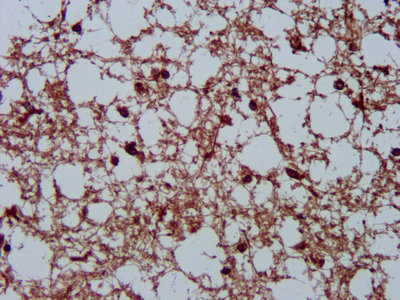

IHC image of CSB-PA05027A0Rb diluted at 1:200 and staining in paraffin-embedded human brain tissue performed on a Leica BondTM system. After dewaxing and hydration, antigen retrieval was mediated by high pressure in a citrate buffer (pH 6.0). Section was blocked with 10% normal goat serum 30min at RT. Then primary antibody (1% BSA) was incubated at 4°C overnight. The primary is detected by a biotinylated secondary antibody and visualized using an HRP conjugated SP system.